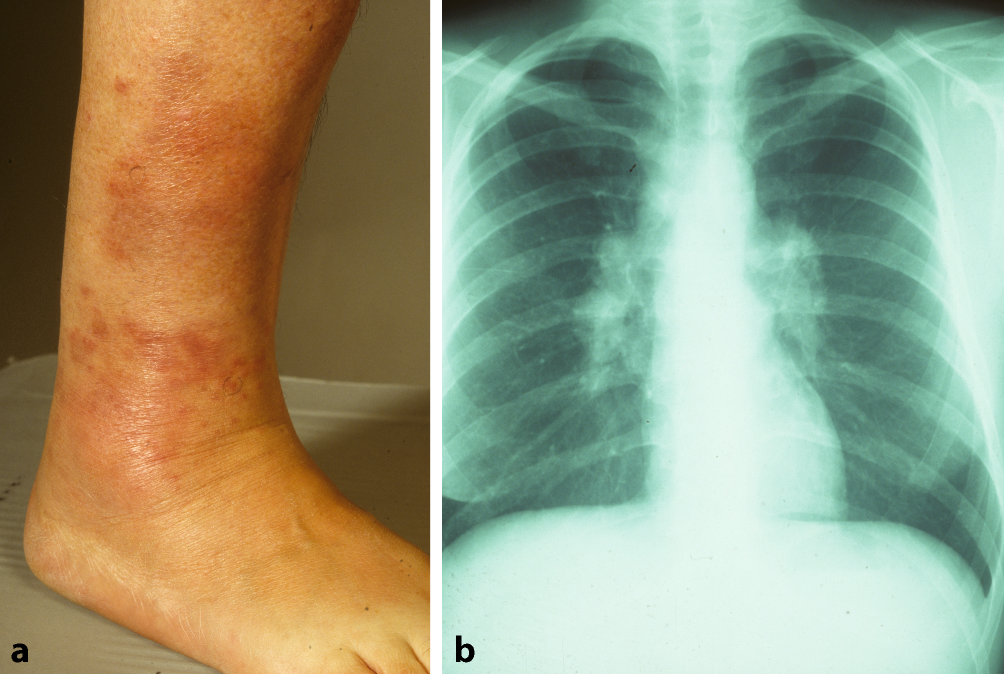

Abb. 3

Löfgren-Syndrom bei einer 63-jährigen Patientin. a Rötliche bis livide Makulae im Bereich des rechten Sprunggelenks (Erythema contusiformis). b Röntgenaufnahme des Thorax mit bihilärer Lymphadenopathie

Bei der Sarkoidose handelt es sich um die häufigste granulomatöse Erkrankung in Nordeuropa. Diese Autoimmun- und Multisystemerkrankung ist der zweithäufigste bekannte Auslöser eines EN weltweit [9]. Etwa ein Viertel aller Sarkoidosepatienten weisen eine Hautbeteiligung auf [1]. Insbesondere ist hier das Löfgren-Syndrom zu nennen, eine Form der akuten Sarkoidose. Klassischerweise wird dies durch die Trias aus Erythema nodosum, Arthritis der Sprunggelenke und bihiläre Lymphadenopathie, häufig in Kombination mit Fieber, definiert. Allerdings gilt es zu beachten, dass bei manchen Patienten weder arthrosonographisch noch magnetresonanztomographisch Zeichen einer Arthritis bzw. ein Gelenkerguss festzustellen sind [10]. Tatsächlich handelt es sich jedoch häufig um eine diffuse, perimalleoläre und nicht zwingend nodöse periartikuläre Pannikulitis, ein sog. kontusiformes („prellungsähnliches“) EN [11]. Diese Veränderungen gehen meist dem typischen Erscheinungsbild des EN im Rahmen eines Löfgren-Syndroms voraus (Abb. 3a). Des Weiteren ist nicht in allen Fällen eine typische bihiläre Lymphadenopathie in der Röntgenübersichtsaufnahme (Abb. 3b) detektierbar, sondern möglicherweise sind entsprechende Befunde hilär und mediastinal erst im Computertomogramm zu sehen.